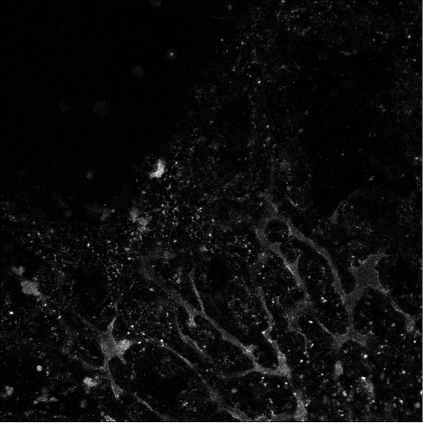

Motivated by the challenging segmentation task of pancreatic tubular networks, this paper tackles two commonly encountered problems in biomedical imaging: Topological consistency of the segmentation, and expensive or difficult annotation. Our contributions are the following: a) We propose a topological score which measures both topological and geometric consistency between the predicted and ground truth segmentations, applied to model selection and validation. b) We provide a full deep-learning methodology for this difficult noisy task on time-series image data. In our method, we first use a semisupervised U-net architecture, applicable to generic segmentation tasks, which jointly trains an autoencoder and a segmentation network. We then use tracking of loops over time to further improve the predicted topology. This semi-supervised approach allows us to utilize unannotated data to learn feature representations that generalize to test data with high variability, in spite of our annotated training data having very limited variation. Our contributions are validated on a challenging segmentation task, locating tubular structures in the fetal pancreas from noisy live imaging confocal microscopy. We show that our semi-supervised model outperforms not only fully supervised and pre-trained models but also an approach which takes topological consistency into account during training. Further, our approach achieves a mean loop score of 0.808 for detecting loops in the fetal pancreas, compared to a U-net trained with clDice with mean loop score 0.762.